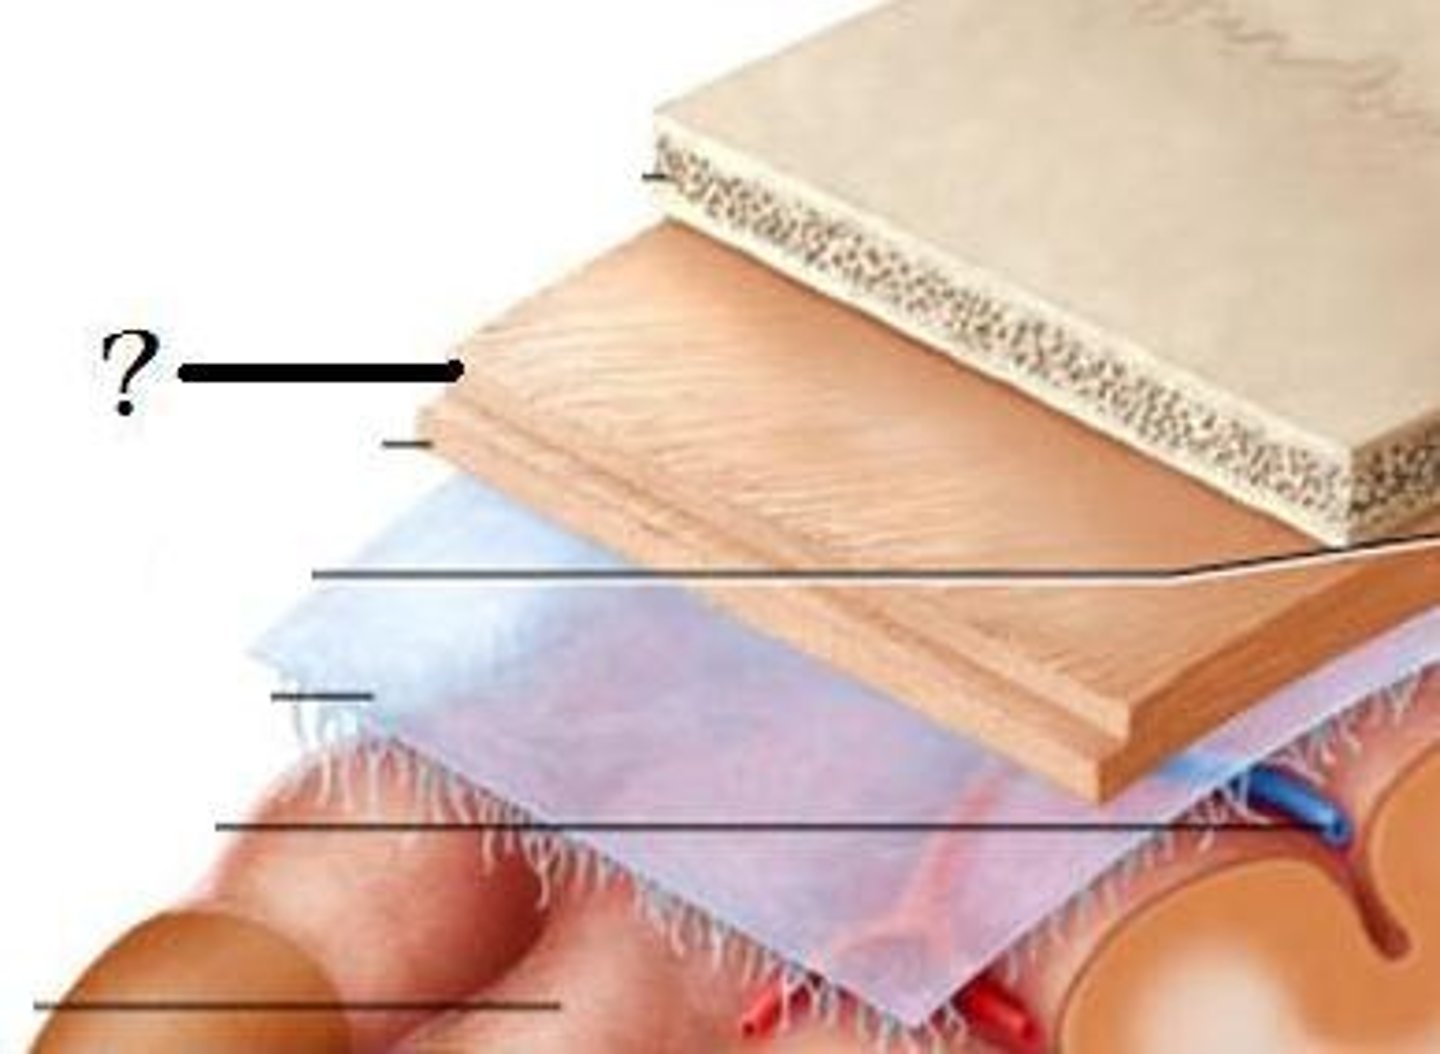

dura mater

periosteal layer

meningeal layer

arachnoid mater

subarachnoid space

with arachnoid trabeculae

pia mater